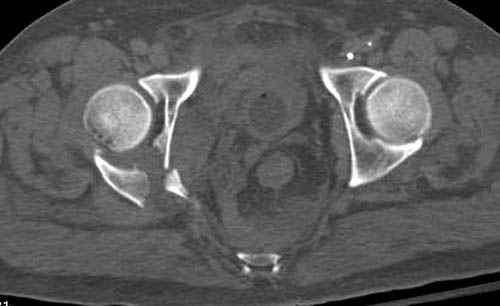

Прооперирован вчера на 13 день после поступления.

Больному 41 и из-за гемодинамической нестабильности в течение первых 7 дней был в реанимации под интубационной седацией.

Кроме перелома плеча у больного старый дистракционный перелом T12-L1 оперированный когда-то и кем-то, открытый перелом костей предплечья, который был прооперирован в ночь поступления, после I&D (хирургической обработки). Из-за разрыва селезенки при поступлении травма хирургами произведено удаление.

Дополнительно имеется перелом ацетабулума: задняя

колонна с полупоперечным переломом, и переломы костей лица.

На седьмой день зафиксирован перелом ацетабулума через задний доступ. Перед операцией для профилактики DVT, IVC фильтер, также получает Lovenox.

Извиняюсь за качества снимков, обычный больной в 300 фунтов, портативным ренген аппаратом не пробить.

Очень хорошаая работа, поздравляю! Хотелось бы увидеть снимок таза до операции. Каким образом и как долго предполагаете разгружать тазобедреннй сустав в дальнейшшем?

Отправитель: Evgueny Tchekashkine 30 Ноябрь 2007, 16:57

По возможности вышлите снимки, сканы таза до реконструкции, интраоперационные.

По снимку создается впечатление о высоком поперечном переломе, задней колонны, стенки; почему не пользовались *magic screw*?

Снимки здесь....